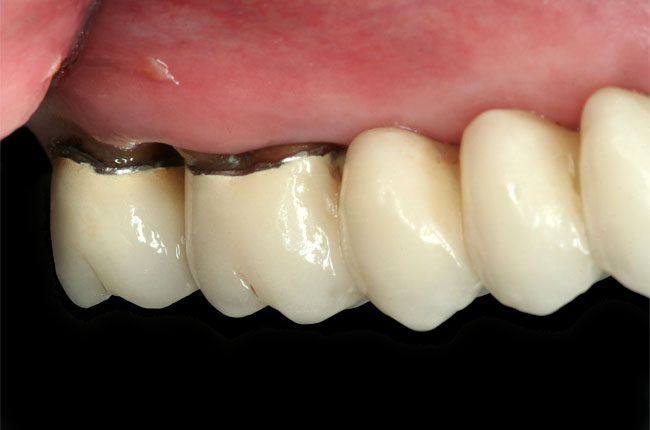

Abbildungen 3-5: Die klinischen Fotographien zeigen den Zustand nach der ersten professionellen Zahnreinigung.

Der komplexe Fall Der komplexe Fall

Abb. 3

Abb. 4

Abb. 5

Abb. 6